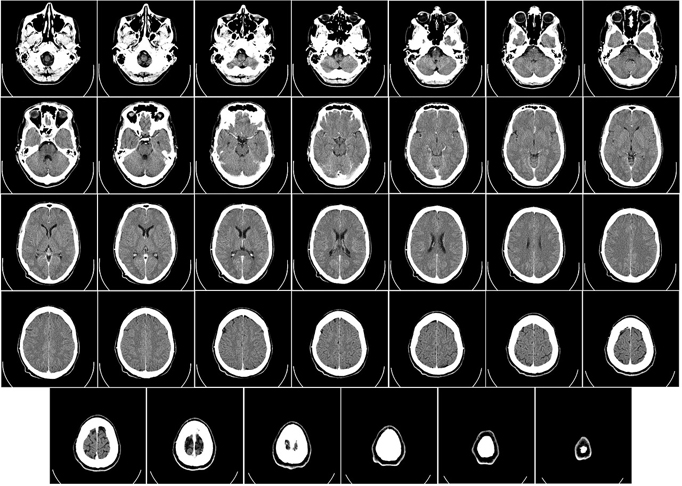

Além da avaliação dos sintomas, o diagnóstico requer exames complementares. Entre eles, tomografia e ressonância magnética. Foto: Imagem de WikiImages por Pixabay -

Os lobos frontais e temporais laterais são as áreas cerebrais mais afetadas.A DFT é uma condição mais rara que outros tipos de demência e a hereditariedade é um fator muito influente. Foto: - Dominio Publico/hippopx.com -

A demência frontotemporal (DFT) é uma doença neurodegenerativa que afeta regiões do cérebro e provoca perda progressiva de funções do órgão. Foto: Tânia Rêgo/Agência Brasil -